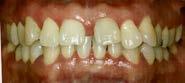

La duración del tratamiento fue de 1 año 9 meses, manteniendo el perfil facial estético y funcional (Figura 9).

Estudios intraorales finales

En las fotografías intraorales finales se ve la corrección del apiñamiento maxilar y mandibular, la forma de las arcadas es ovalada, se consiguió guía de desoclusión canina derecha e izquierda, la mordida profunda

anterior (Figura 10), la estabilidad oclusal, la máxima intercuspidación, el paralelismo radicular y oclusión funcional, el cierre de diastema ante rior, las líneas medias superior-infe rior coincidieron ambas con la facial.

Manejo de maloclusión de mordida profunda y diastema anterior Figura 6. Intraoral de frente, derecha, izquierda. Figura 7. Intraoral de frente, derecha, izquierda.

mediante extrusión de los dientes posteriores y la intrusión de los dien tes anteriores.3,13-15 Siguiendo el pro tocolo G5 de Invisalign en el paciente del CESO se corrigió la mordida pro funda, con el cierre del diastema anterior se llevó a la coincidencia de las líneas medias maxilar y man dibular. Terminando con una línea de sonrisa armónica, manteniéndose la simetría facial.

Figura 8. Vista oclusal forma de las arcadas oval con termo formador superior e inferior. Figura 9. Extraoral de frente, final. Figura 10. Comparación frente inicio, vista oclusal superior e inferior, en oclusión lado derecho izquierdo final.